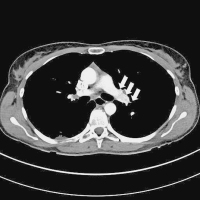

Rechtsherzbelastung

Abbildung 4a-b: Rechtsherzbelastung mit massiver rechtsventrikulärer Dilatation auf 40 mm in der Akutphase (linkes Bild; Pfeile) und CT-Verlaufskontrolle nach 6 Monaten mit nun wieder normal großem (28 mm) und tailliertem rechten Ventrikel (rechtes Bild; Pfeile)